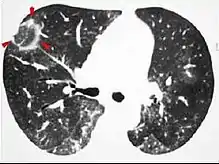

High-resolution CT image showing ground-glass opacities in the periphery of both lungs in a patient with COVID-19 (red arrows). The adjacent normal lung tissue with lower attenuation appears as darker areas.